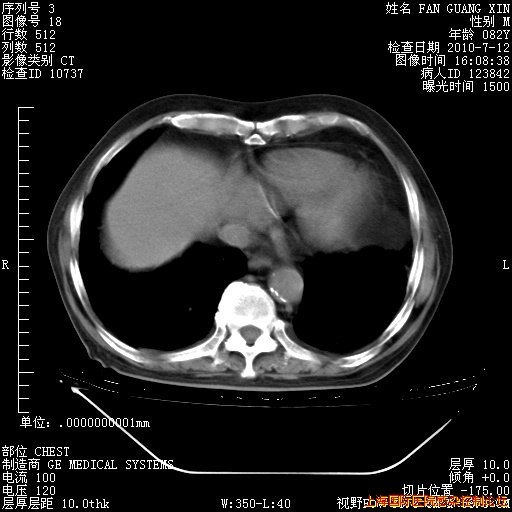

今天复查CT

今天CT

整整相隔30天的肺部CT好像有所好转啊。甲强龙减量第3天,需要观察体温。

海管,自昨日你和我通完话后,不知您岳父消化道症状有无缓解?体温怎样?阅读7.12日胸部ct,个人认为目前激素治疗是有效的,甲强龙减量是适宜的。因在抗痨治疗,需密切观察肝功、肾功能和血常规。不过,老年、长期住院和大量使用激素,很担心菌群失调发生